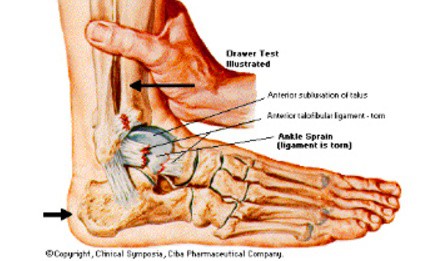

발목 염좌

발목 염좌는 연조직 손상때문에 발생합니다. 이는 심각한정도에따라 발목통증의 정도가 다릅니다.

염좌는 인대가 늘어나거나 찢어져서 발생합니다.

발목은 매일 많은 움직임을 받으므로 항상 염좌의 위험이 있습니다.

발목 염좌의 증상은 아래와 같습니다

- 발목 관절의 소리

- 붓기

- 움직일때 통증

주로 스포츠 경기나 운동중 부상으로 발생합니다.